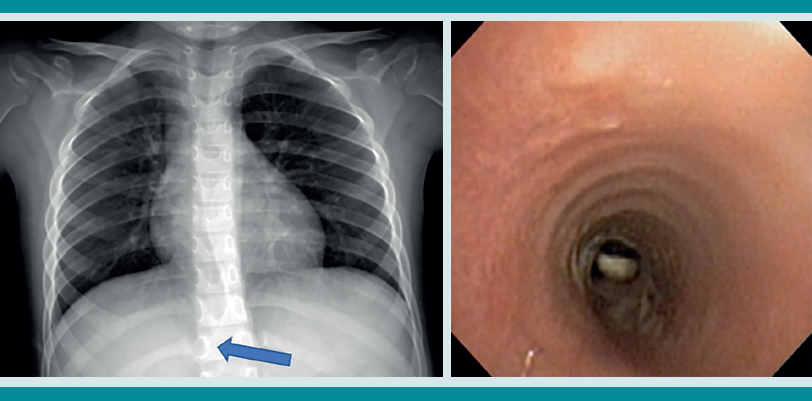

La radiografía de tórax es el primer estudio en un paciente pediátrico que llega al servicio de urgencias con sospecha de aspiración de cuerpo extraño. Gran parte de los objetos aspirados son radiolúcidos (biológicos y plásticos) y, por lo tanto, no se ven por este medio. Solo se logrará observar el cuerpo extraño en 15% de los casos (metálicos y huesos).1,6,8 Es más común identificar datos indirectos (aparecen hasta en 50% de las radiografías), que son consecuencia de la obstrucción en la vía aérea (atrapamiento de aire, atelectasias, consolidación, neumotórax) (Figuras 1,2,3,4,5). Respecto de las radiografías de tórax es que, incluso 45% pueden interpretarse normales, lo que puede resultar en un diagnóstico erróneo.1,6,9

Si al momento de consultar el paciente se encuentra en la etapa aguda, pero está estable, es decir, sin datos clínicos de inestabilidad cardiorrespiratoria, o se encuentra en la etapa oligosintomática pueden solicitarse los estudios de imagen. La radiografía de tórax es el principal recurso con el que cuentan la mayor parte de los servicios de urgencias. Es rápido, fácil, poco costoso y no requiere sedación. En caso de que sea un objeto radio-opaco, aportará el diagnóstico de manera rápida, y dará la localización del objeto (Figura 7). En caso de ser radiolúcido, la radiografía puede ser normal o mostrar los datos indirectos de obstrucción comentados. La tomografía axial computada de tórax puede considerarse si se cuenta con el recurso, tomando en cuenta lo mencionado.